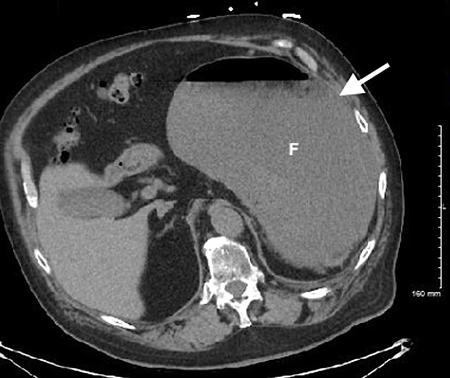

腹部床旁超声检查(POCUS)显示,胃部扩张并充满液体,高度疑似梗阻(图1,2)。

(图1 POCUS检查显示胃部膨胀充满液体[星号])

当怀疑有胃扭转时,选择初始的影像学检查非常重要,因为诊断延迟可能导致致命的并发症。CT检查高度可靠,主要有两种表现,即正常的胃窦幽门移行区和胃窦位置异常,诊断急性胃扭转的敏感性和特异性均为100%。POCUS是一种有效的非侵入性影像检查方式,主要用于床旁评估。此外,POCUS无辐射,并可根据临床情况随时进行重复检查。本例患者POCUS检查显示,胃部严重扩张,胃内容物分层,类似胃出口梗阻(GOO)的“黑白饼干”征象。POCUS还可以用来动态观察胃减压成功与否。